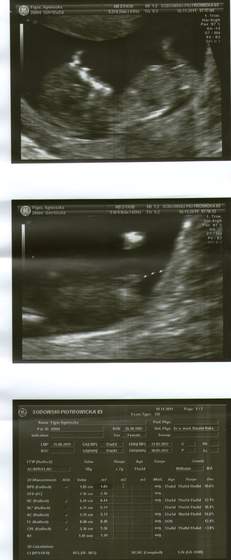

super zdjecia Agagu,az zazdroszcze takich dokladnych!!!nie to co moje rozmazane!super fotki

i gratuluje coreczki!!

Śliczne foteczki